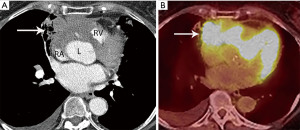

Thymoma typically presents as a smooth or lobular mass involving one lobe of the thymus, although bilateral involvement can occur (39). Most thymomas demonstrate homogeneous enhancement, although, approximately one third can be heterogeneous due to areas of hemorrhage, necrosis, cystic change, or calcification (1) (Figures 8,9). Imaging characteristics can vary according to WHO histological classification, with vascular invasion and pleural/pericardial involvement more common with more aggressive histology (Figure 2). The thymomas with the more aggressive histologies tend to be larger, more lobular or irregular, have cystic or necrotic change, areas of calcification, or evidence of infiltration into surrounding fat (40-42) (Figure 10).

On MRI, thymomas have low to intermediate signal intensity on T1 weighted images and high signal intensity on T2 weighted images. If areas of cystic change or necrosis are present, these have decreased T1 signal intensity and increased T2 signal intensity. Fat suppression imaging can delineate thymomas from mediastinal fat which facilitates more exact measurements and enhancement evaluation. MRI is more limited than CT for calcification detection. MRI strengths include identifying nodules, thickened septae, and/or thickened capsule in cystic thymoma and differentiating cystic thymomas from benign prevascular thymic or pericardial cysts. Because of its superior contrast resolution, MRI also excels in identifying direct cardiac involvement compared to CT (43).

The role of FDG PET/CT in thymoma imaging is limited. Given the presence of FDG uptake in the normal and hyperplastic thymus, especially in younger adults and children, false-positive results can occur. In fact, physiologic uptake has been reported in 28% of patients under 40 years of age and up to 73% in children less than 13 years of age (44). PET/CT has not been shown to differentiate different WHO histological classifications of thymic tumors, although the more aggressive histologies tend towards higher FDG uptake (45,46) (Figures 2,3). Indium111 octreotide nuclear medicine scans have now been replaced by 68Ga-labeled somatostatin analogues because 68Ga-labeled somatostatin analogues, such as 68Ga-DOTATATE, are used for PET/CT, and thus provide better resolution.